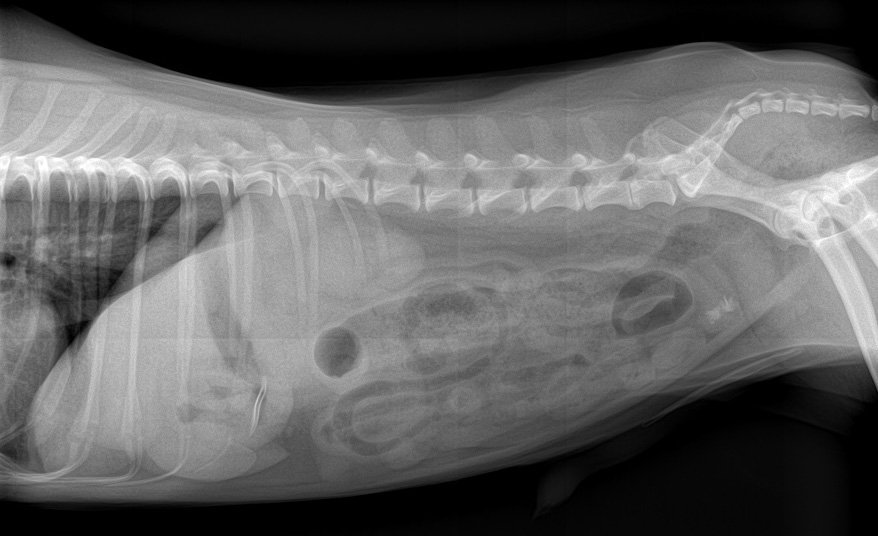

Lat G